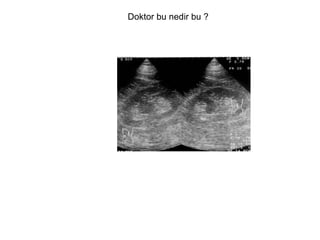

Doktor bu nedir bu ?

Hypertrophied column of Bertin.  (adamlar radyoizotop görünteleme  ile bu tanıyı doğrulamışlar peki nedir bertin  Hatırlayan varmı ?